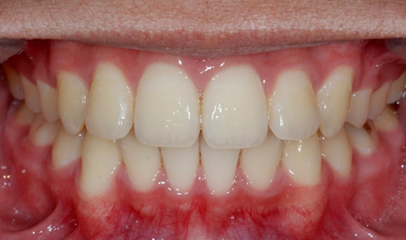

발치 돌출입 교정

전후 사례

발치 교정, 치료기간 약 2년

After